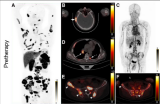

中国临床启动在即,靶向PSMA的抗体核素偶联药物TLX591全球III期研究进入新阶段

Telix Pharmaceuticals公司今日宣布,其针对转移性去势抵抗性前列腺癌(mCRPC)的主要在研疗法TLX591(177Lurosopatamab tetraxetan)的ProstACT全球III期研究已取得重要进展。该研究的第二部分(随机治疗扩展阶段)首位患者已在澳大利亚墨尔本的前列腺癌中心完成给药。ProstACT全球研究是首个将PSMA靶向放射性抗体偶联药物(rADC)疗法与标准治疗(SOC),包括阿比特龙、恩扎卢胺或多西他赛联合使用,并与单独使用标准治疗进行对比的III期试验。第. 2025-12-08 核医学核医药放射性药物